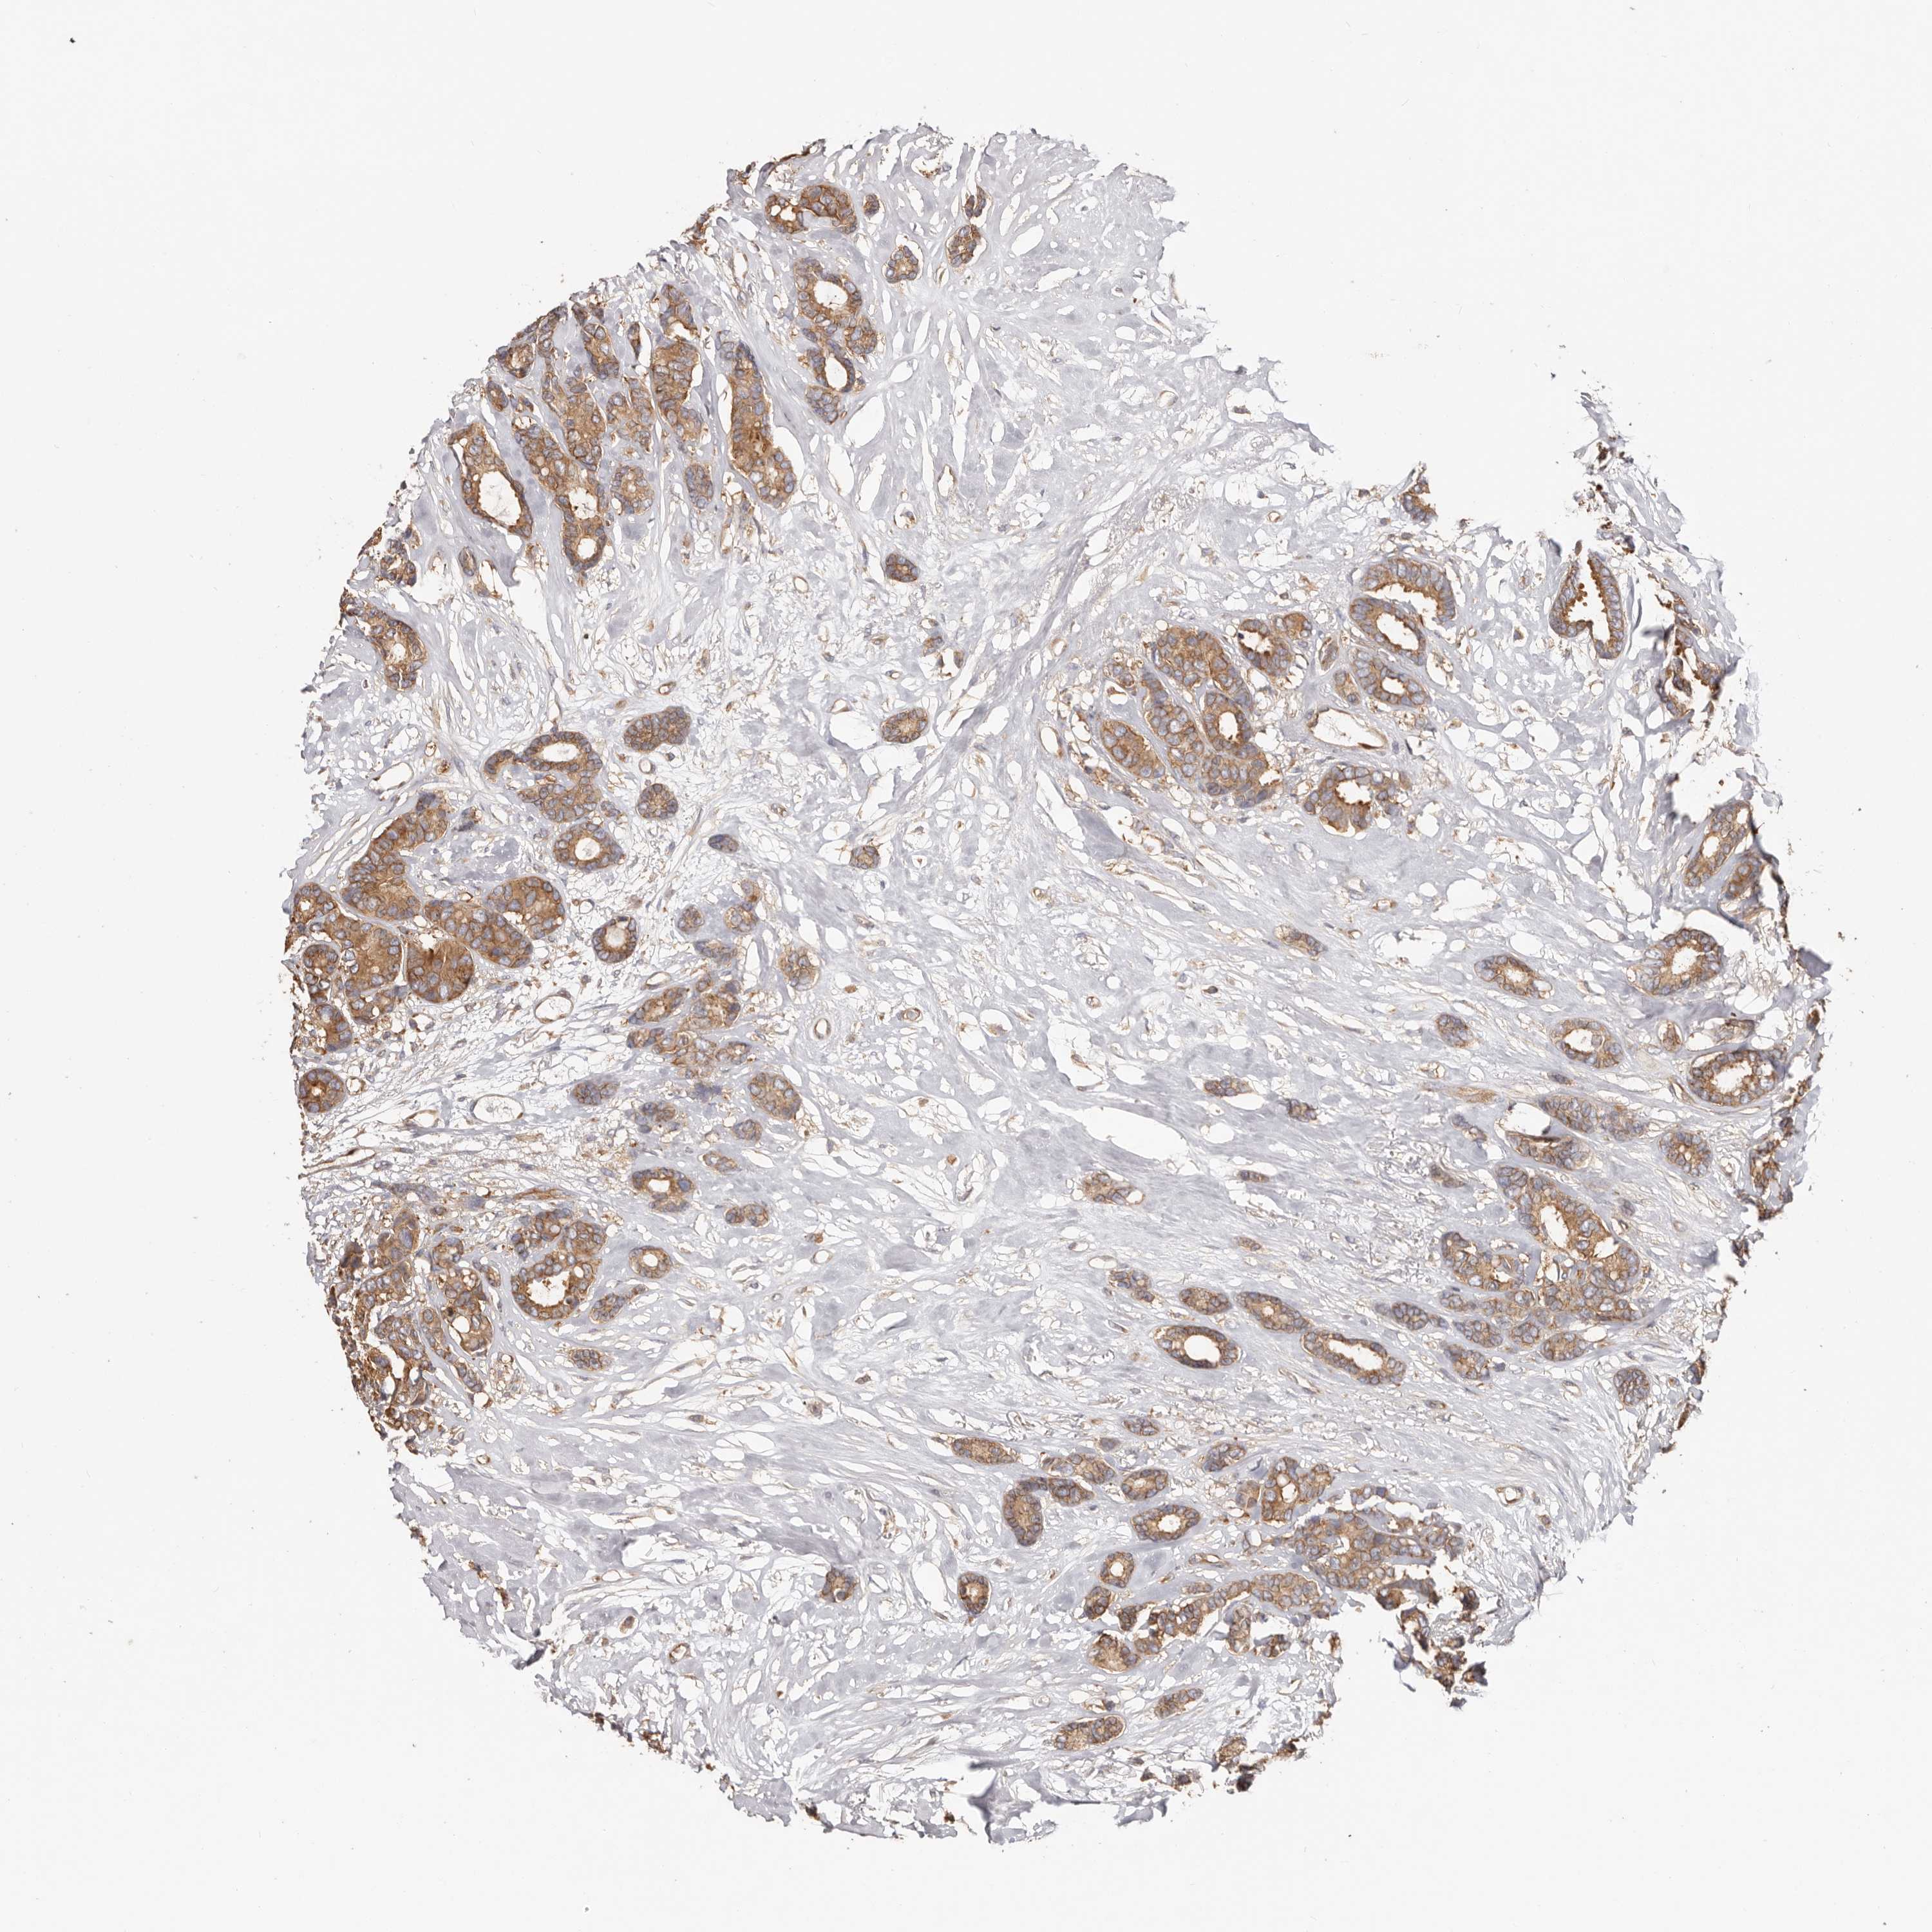

CANCER BREAST CANCER Show tissue menu

BRCA TCGA BRCA VALIDATION PROTEIN EXPRESSION

EPRS1 is not prognostic in Breast Invasive Carcinoma (TCGA)